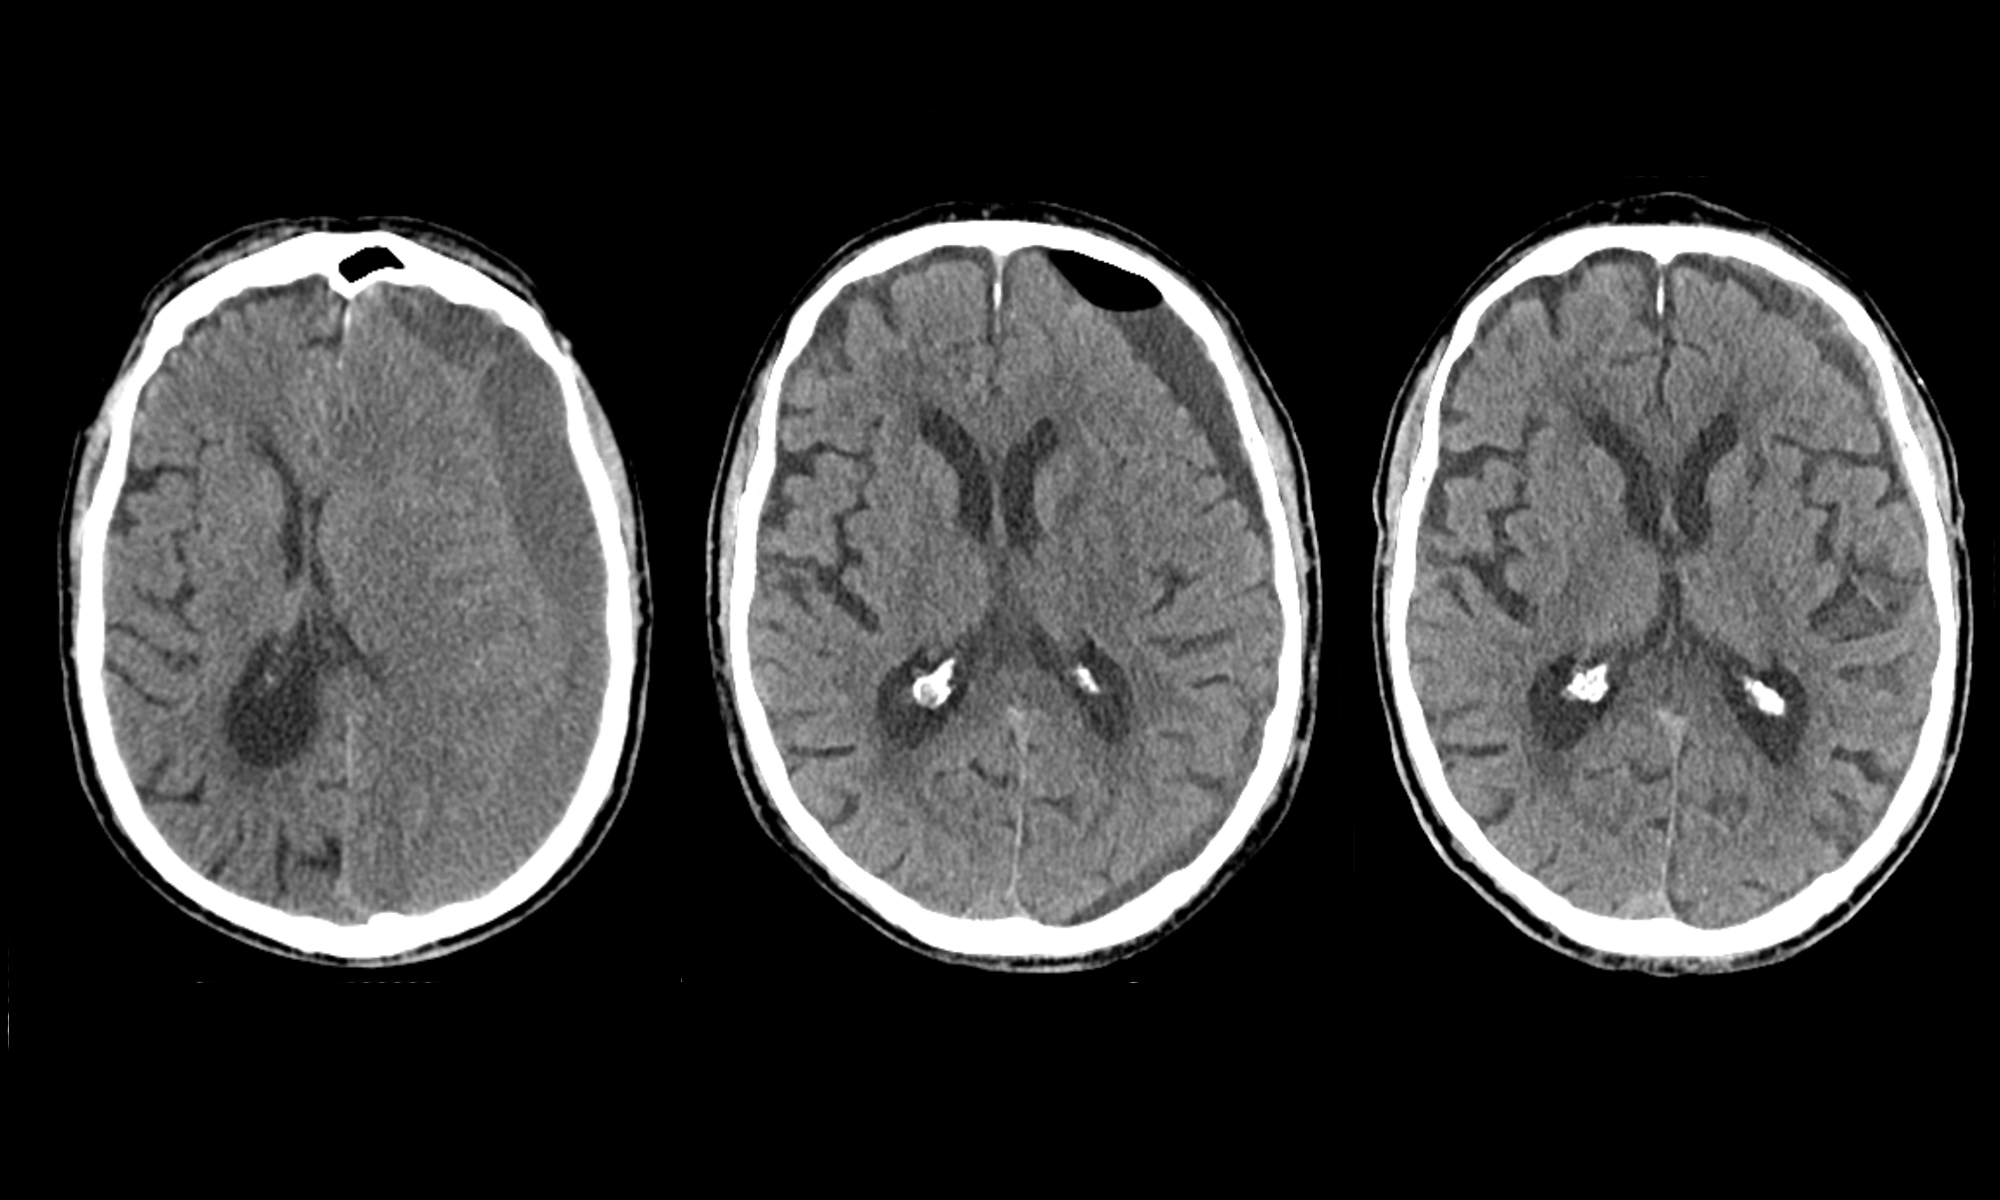

Das chronische Subduralhämatom ist eine häufige Blutung zwischen dem Gehirn und dem Schädel. Sie entsteht meistens bei älteren Menschen, die einen Blutverdünner nehmen, durch einen Aufprall auf den Kopf. In einer relativ einfachen Operation mit zwei kleinen Löchern kann das Blut abgelassen werden, und rund 80 Prozent der Patienten werden dadurch geheilt. Bei einer Minderheit kommt es trotz der Operation zu einer erneuten Blutung am gleichen Ort, und die Operation muss Tage bis Wochen später wiederholt werden. Um vorherzusehen, wer eine zweite Operation benötigt, wird meist eine Computertomographie (CT) durchgeführt, die zeigt, wie viel Blut nach der Operation sich noch zwischen Gehirn und Schädel befindet. Forschende des Neurozentrums am Inselspital, Universitätsspital Bern haben hinterfragt, wie gut diese Bilder überhaupt zur Vorhersage nützen.

Erstautor Prof. Dr. med. Philippe Schucht erklärt die Ergebnisse: «Wenn wir nach der Operation ein CT machen, sieht man eigentlich bei allen Patienten noch Blut um das Gehirn herum. Als behandelnder Arzt ist man versucht, für den Patienten ein ‘besseres’ Resultat durch eine zweite Operation zu erreichen, auch um zu verhindern, dass der Patient wieder Beschwerden bekommt. Dieses Restblut wird jedoch bei den meisten Patienten vom Körper mit der Zeit abgebaut, weshalb eine Voraussage ob es später nochmals eine Operation braucht, schwierig ist. Falls die Blutung mit der Zeit wieder langsam zunimmt, bemerken die Betroffenen wieder mehr Kopfschmerzen oder eine Schwäche. Dann haben wir immer noch Zeit zu untersuchen und ein CT zu machen – aber nur dort, wo es wirklich nötig ist.»